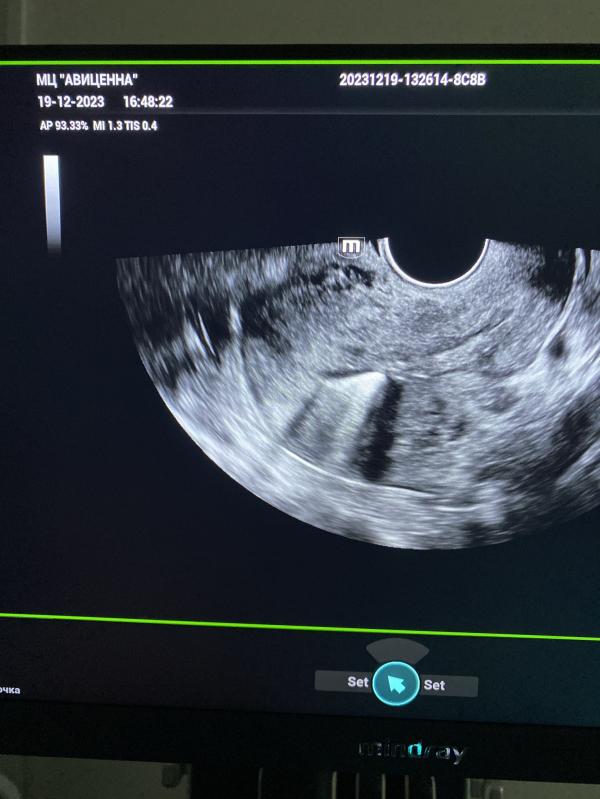

Какие осложнения могут быть от внутриматочной спирали, эрозии, полипы шейки матки и кондиломы?

В полости матки круглая спираль.

Эрозии, полипы шейки матки и много кондилом 😌 все успела сделать